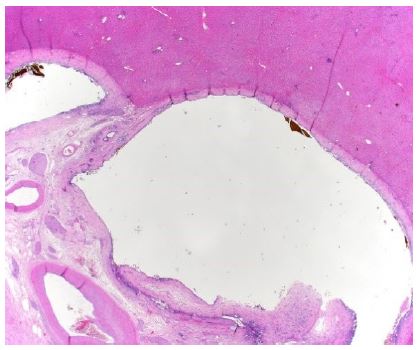

Histology of the surgical specimen revealed surprising findings: There was no evidence of neoplasia. However, several peribiliary cysts, so called “Nakanuma cysts”, could be identified (Figure 5), including one large extrahepatic cyst (Figure 6), and multiple smaller cysts (Figure 7) in the left lobe, causing stricture of the left bile duct with consecutive cholestasis, hepatolithiasis and cholangitis leading to cholangiosepsis.

Figure 6: Microscopic image of extrahepatic cyst.